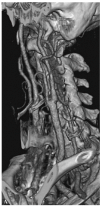

Fig. 3. --(A) Imagen de reconstrucción volumen rendering. (B) Reconstrucción mini-MIP de la arteria carótida izquierda. Estudio de angio-CT donde se observa la bifurcación carotídea y la porción proximal de ACI sin ninguna estenosis de significación.